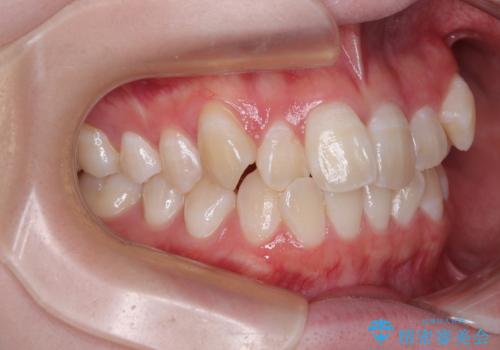

- 「前歯のデコボコ(叢生)をきれいに整えたい」とのことでご来院されました。

目立ちにくさと費用のバランスを考慮し、プラスチックブラケット+メタルワイヤーを採用。日常生活でも装置の存在感を気にせずお過ごしいただけます。

患者様の協力もあり、およそ1年間で治療を完了。スムーズな歯の移動を実現しました。

上下の正中(真ん中のライン)もずれることなく、バランスの取れた美しい歯並びに。笑顔に自信を持てる仕上がりとなりました。